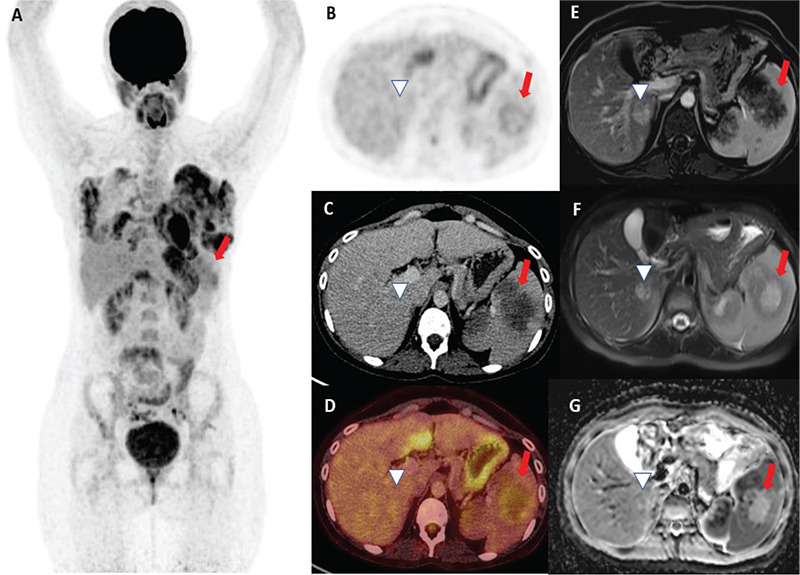

Peliosis hepatis (PH) and sclerosing angiomatoid nodular transformation of the spleen are uncommon benign lesions. Diagnosis can be difficult in some patients. Herein, we present the case of a 28-year-old woman referred with abdominal pain who had spleen lesions. 18F-fluorodeoxyglucose (FDG) positron emission tomography/computed tomography revealed multiple non-FDG avid lesions in the liver and hypermetabolic lesions in the spleen. In addition, abdominal magnetic resonance imaging was performed. Histopathology revealed sclerosing angiomatoid nodular transformation in the spleen and PH in the liver.